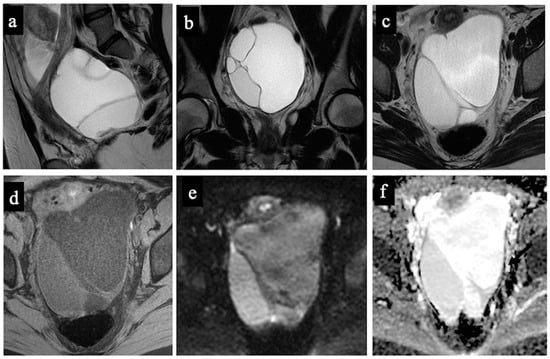

Figure 2. Decidualised endometrioma. MR images of a 34-year-old woman—20 weeks pregnant—with an indeterminate adnexal lesion discovered at the 16-week US. The coronal T2-WI (a), axial T1 (b), T1-WI with fat-saturation (c), T2-WI (d), DWI (e) and ADC-map images (f) show a unilocular cystic right adnexal mass with haemorrhagic content (high signal intensity on the T1-WI, T2-WI, and T1 with fat saturation). This was considered a false positive since both readers misclassified the mass as malignant/score 4 due to the presence of tissue with true diffusion restriction along the lesion’s right lateral wall (arrow). Note the gestational sac in the uterine cavity (asterisk).

Figure 3. Borderline mucinous cystadenoma. MR images of a 28-year-old woman—17 weeks pregnant—with an indeterminate adnexal lesion discovered at the first-trimester US. The sagittal (a), coronal (b), and axial T2-WIs (c), T1-WI with fat-saturation (d), DWI (e) and ADC-map images (f) show a multilocular cystic left adnexal mass with different signal intensities within the loculi. Both readers considered this lesion as benign/score 3 (probable mucinous cystadenoma) because no solid tissue was found (false negative).